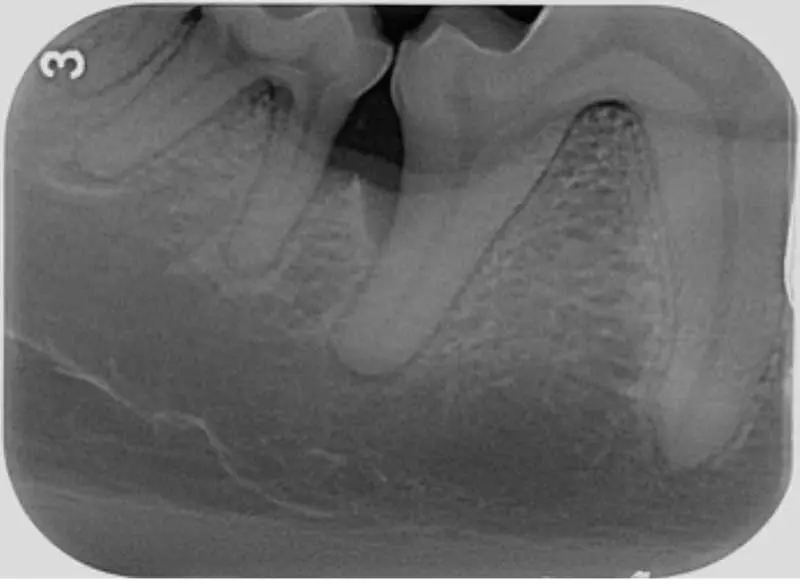

Dental radiography

- Used to identify and evaluate bone loss, identify periapical pathology and assist in treatment planning. It also helps veterinarians determine if any areas of concern require closer monitoring or more aggressive treatment.

- Monitoring progress. X-rays are helpful for tracking the progress of periodontal disease over time. Follow-up radiographs can show whether the disease is progressing or if the treatment (such as ultrasonic scaling, root planing, guided tissue regeneration or tooth extractions) has been effective (Figure 8).